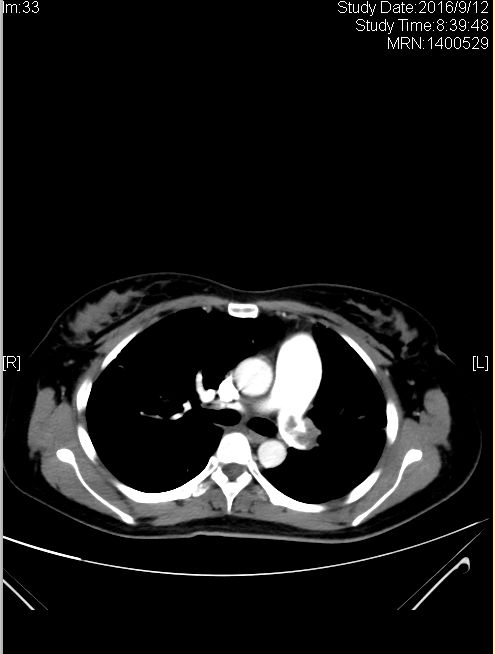

患者女,31岁,因“反复咳嗽、咳痰、痰中带血、气喘5月,加重7天,发热1天”于呼吸科就诊,心脏彩超及8月4日胸部CTA图1示肺栓塞,D-二聚体3.53mg/L,FDP13.24mg/L支持肺栓塞表现,5日置管溶栓,9月12日复查图2示好转,10月27日再次入住呼吸科,胸部CTA图3示栓子增多,查自身免疫系列、常规化学、G试验、病毒全套、甲状腺功能、肿瘤标志物等无明显异常,至此,该病人的诊断就陷入了困境,这个病人出现反复肺栓塞的原因究竟是什么呢?

图2